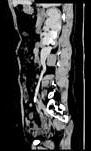

问题 女,44岁,突发性胁腹部绞痛并向会阴部放射伴血尿一次。如图所示,下列说法正确的是 ( )

选项 A、右输尿管结石 B、左肾输尿管未见异常 C、右输尿管中上段扩张 D、右输尿管内可见沿输尿管走行的高密度影 E、右侧肾盂肾盏扩张

答案 ABCDE